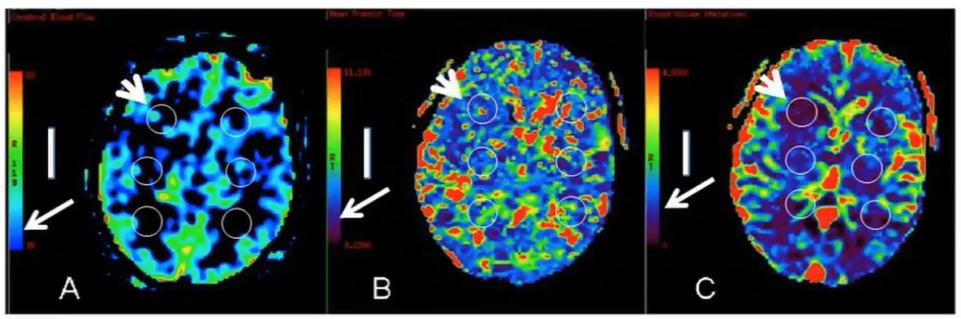

在一篇文献中,一例多发分水岭梗死的CADASIL患者的磁共振灌注发现双侧深部白质低灌注:脑血流量下降(A)、平均通过时间延长(B)及脑血容量下降(C)。